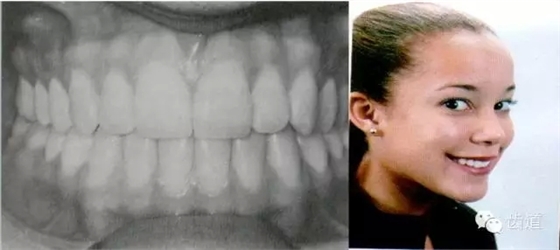

典型面形

上頜第一磨牙的近中頰尖位于下頜第一磨牙的頰溝近中

典型面形為下頜后縮面形

上頜第一磨牙的近中頰尖位于,下頜第一磨牙的頰溝遠中

典型面形為下頜前突面形